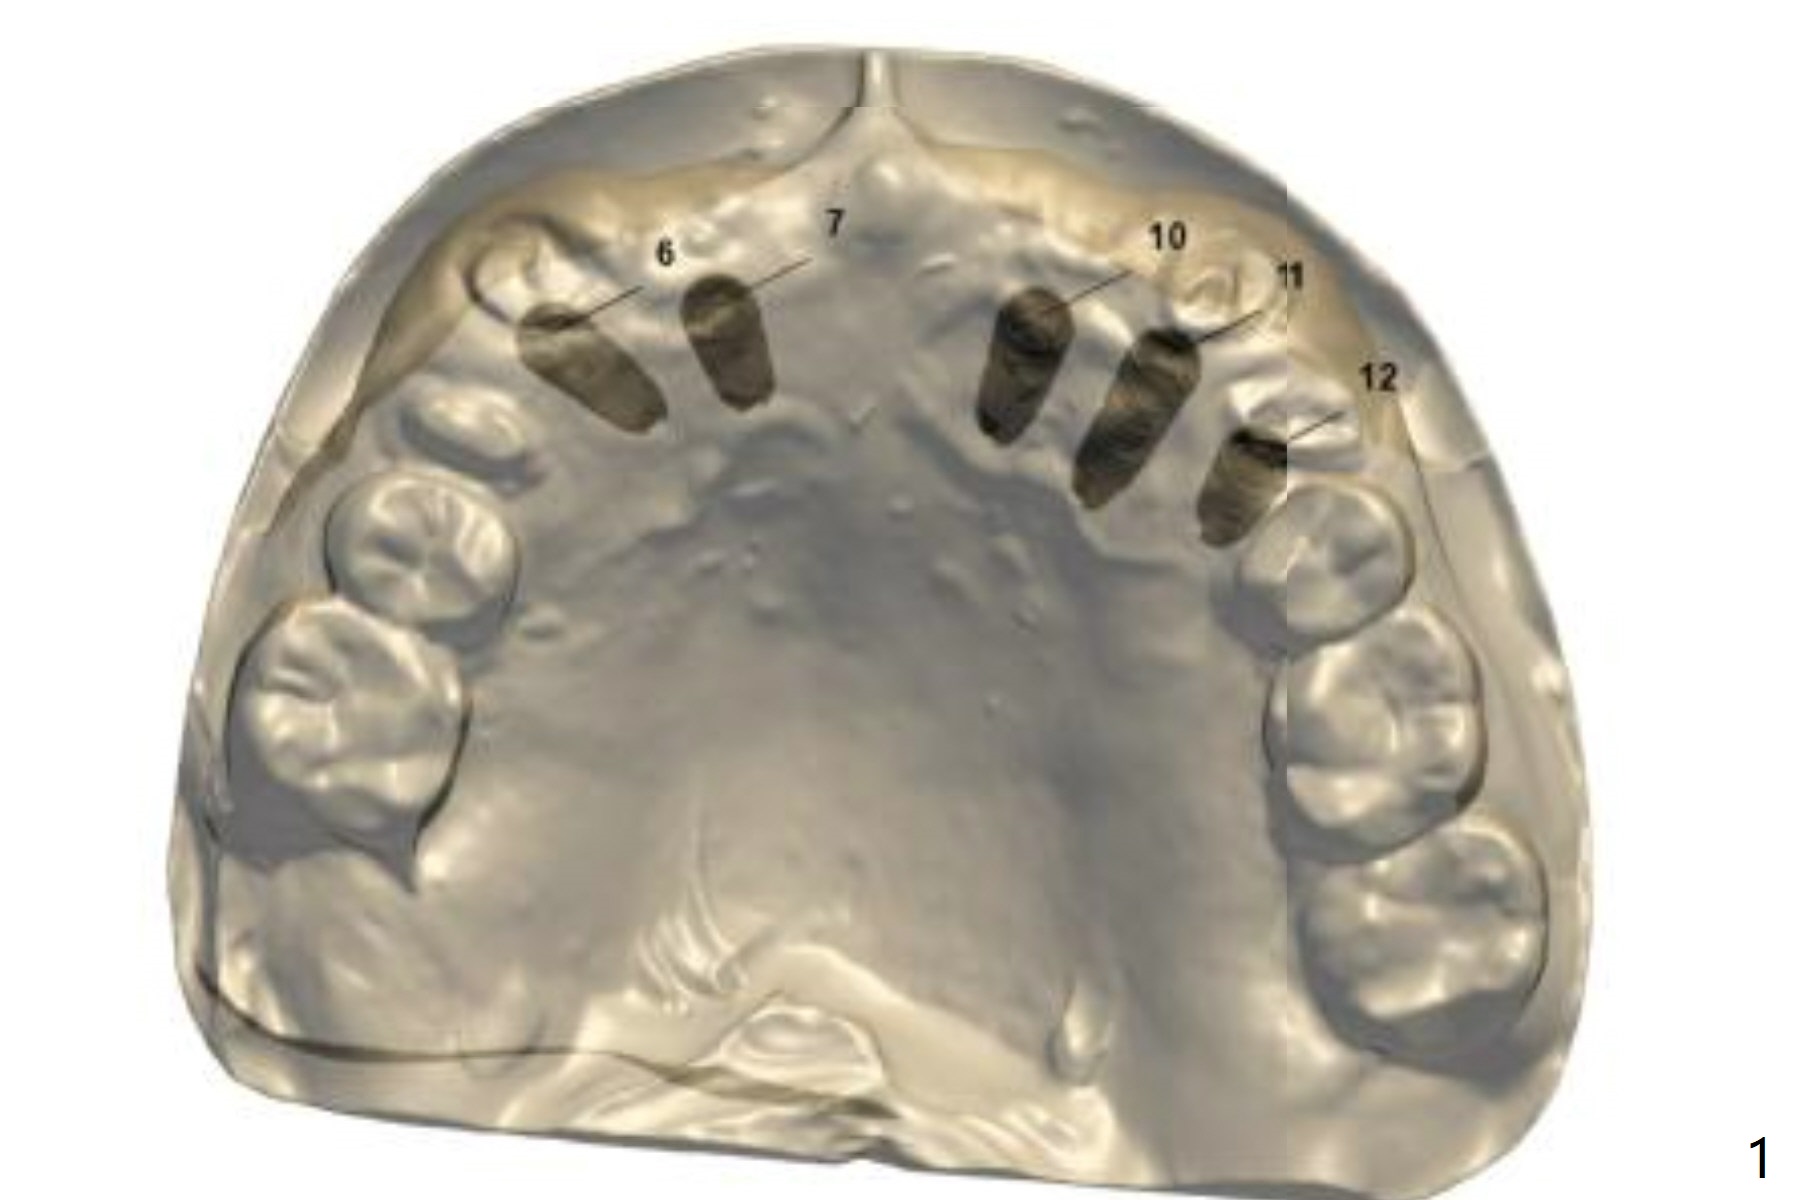

Since the apex of the tooth #5 seems to tilt mesial, implants at #6 and 7 will be placed mesial intentionally with diameters of 3.5 and 3 mm (Fig.1-3). On the left side with minor space issue, two-piece implants with 3.5 mm in diameter will be placed at #11-12 (Fig.5-6). After implant osteointegration, a 4-unit FPD will be fabricated between #7-10. Return to Upper Arch Immediate Implant, Trajectory, Metronidazole Xin Wei, DDS, PhD, MS 1st edition 11/09/2018, last revision 11/16/2018